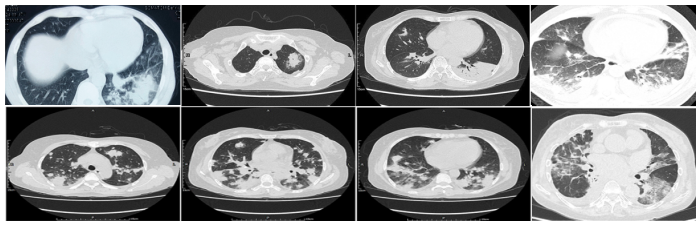

AFOP的影像学表现也缺乏特异性,大多表现为多个边界不清的结节和实变区域,以支气管血管周围和基底为主,呈不规则斑片状实变;多数双侧受累;少部分表现为磨玻璃影(GGO)及结节影;胸膜受累少见,少数存在胸腔和心包积液。

图片

图2  AFOP影像学表现

有学者总结了AFOP的影像学特征:大部分(77%)为双肺下叶、外周分布,60.3%为大片状实变影,22.2%为磨玻璃影,11.1%为网格或线样征,6.3%为结节影。